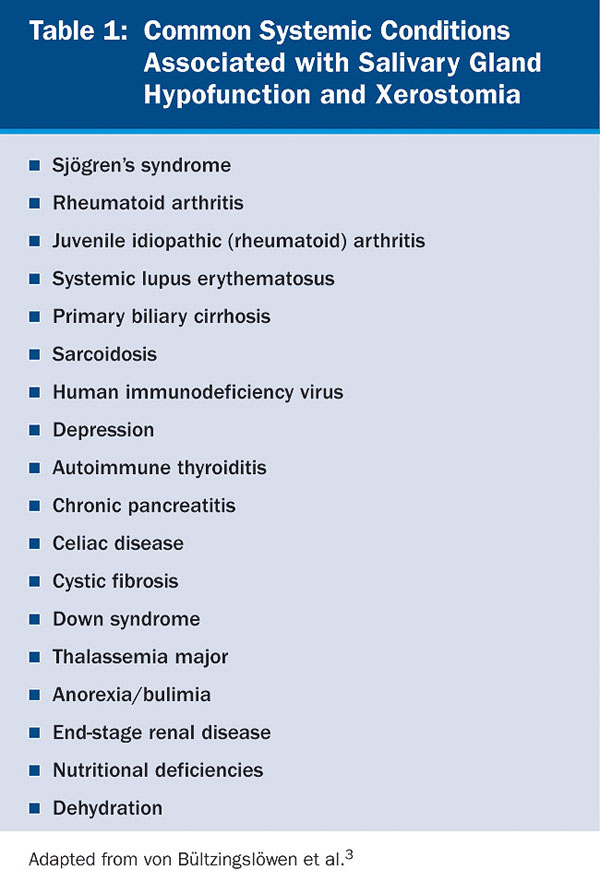

Aging per se has no significant impact on salivary gland secretion.12 In the elderly, several factors, such as decrease of ptyalin, increase of mucin, and low stimulation of the peripheral receptors, have been implicated in xerostomia.13 Xerostomia and/or salivary gland hypofunction in this population has been associated with a number of systemic disorders (Table 1) and medications14,15 (Table 2). The incidence increases with medication exposure,16 with more than 400 drugs implicated.2 In a 5-year longitudinal study, the relationship of dry mouth and long-term exposure to medications was assessed. Xerostomia severity was found to be higher among females and associated with the use of medications, such as antianginal, diuretics, antidepressants, and antiasthma, as well as thyroxine.17 Xerostomia and salivary gland hypofunction are also major complications of radiation or chemotherapy. Long-term morbidity in patients receiving combined radiation and chemotherapy is significant because of xerostomia, salivary gland hypofunction, and severe dysphagia.18